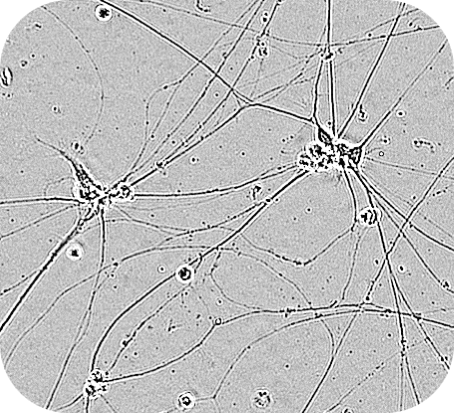

共培養モデル・神経炎症モデル (ミクログリア × アストロサイト × 神経細胞)

ミクログリア x アストロサイト x 神経細胞の3者共培養により、脳内環境を再現し、神経炎症カスケードの可視化や、Ca2+イメージングにて神経活動評価が可能です。